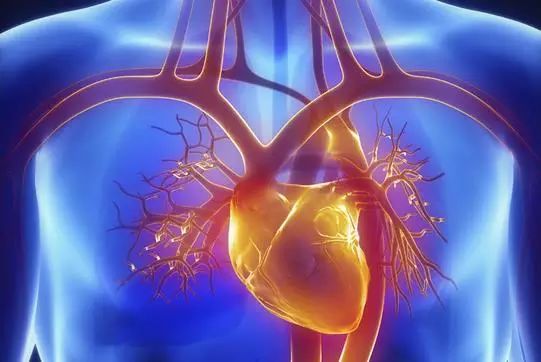

5、心脏——排除冠心病用CT,看心功能用超声

常规的心脏结构与功能检查,心脏彩超所提供的信息已经较为充分,又简单易行。

用CT可检查冠状动脉,但冠脉CT检查辐射量较大,不适合作为常规体检。核磁虽无电磁辐射,但对冠状动脉的观察不及CT。心脏核磁则是评价心脏结构和功能的“金标准”。